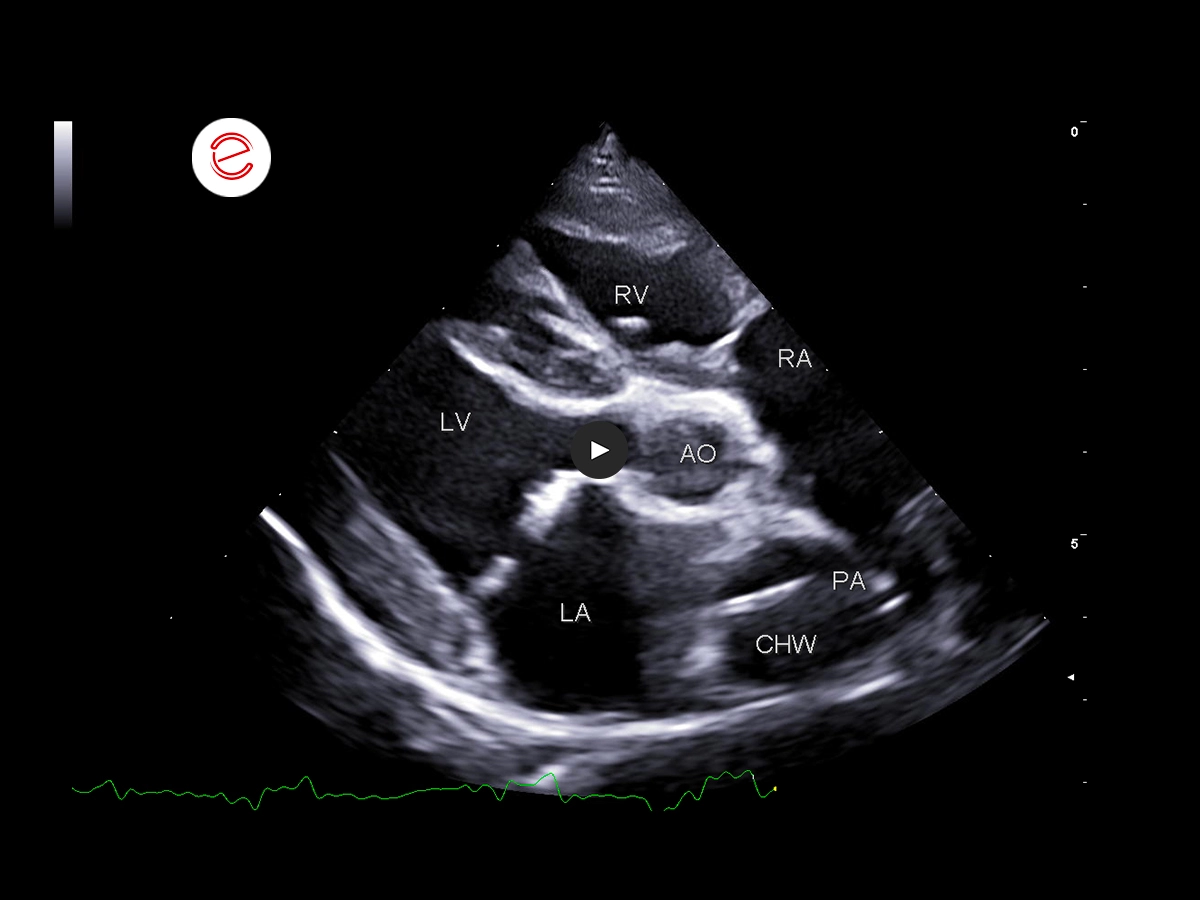

On the right parasternal long-axis 5-chamber view, these echogenic parallel lines within the dilated pulmonary artery are highly suggestive of the presence of adult Dirofilaria immitis.

On the right parasternal short axis view at the heart base, echogenic parallel lines suggestive of adult Dirofilaria immitis are seen within the main pulmonary artery and right ventricular outflow tract.